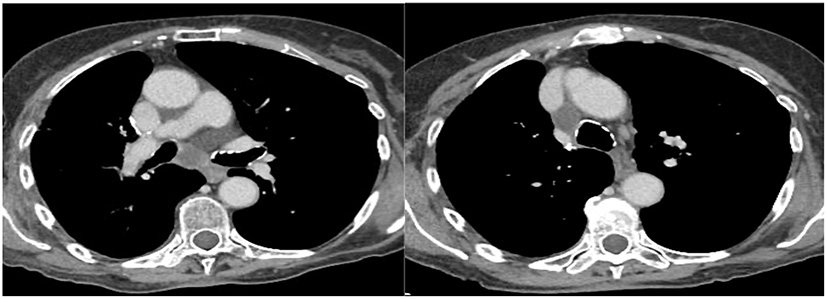

During follow-up, all these patients were referred to “Ospedali Riuniti di Ancona” (n = 7) and “Ospedale San Martino” (Genoa) (n = 1) Interventional Pulmonology Units for the characterization of new onset hilar and/or mediastinal lymphadenopathies detected by imaging with CT LN enlargement (Figure 1) and intense metabolic activity on PET/CT (Figure 2).

Figure 1

Subcarinal (7) and right inferior paratracheal (4R) lymphadenomegaly.